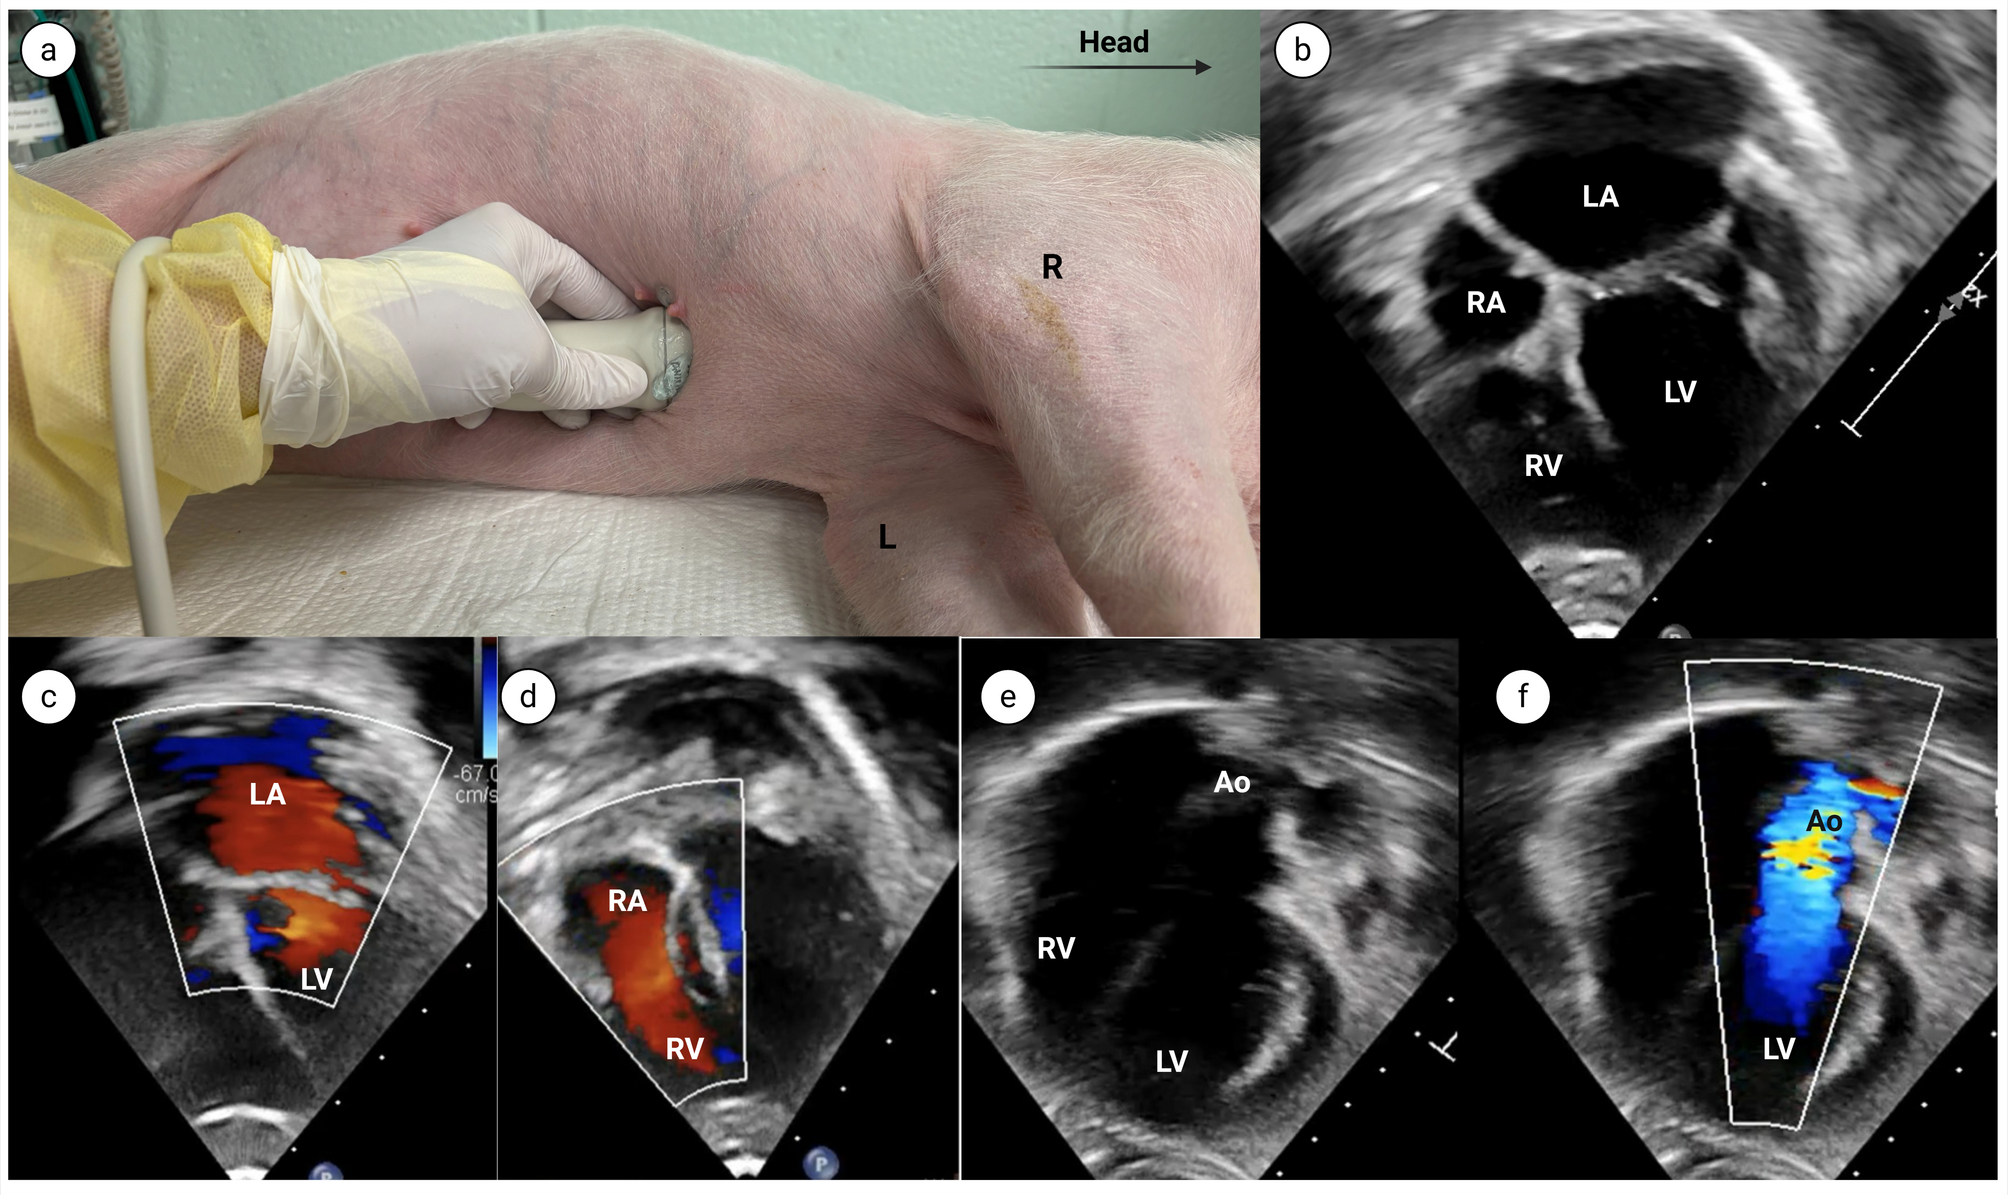

From: Transthoracic echocardiography for evaluating cardiac parameters in growing piglets

Apical 4 chamber view.